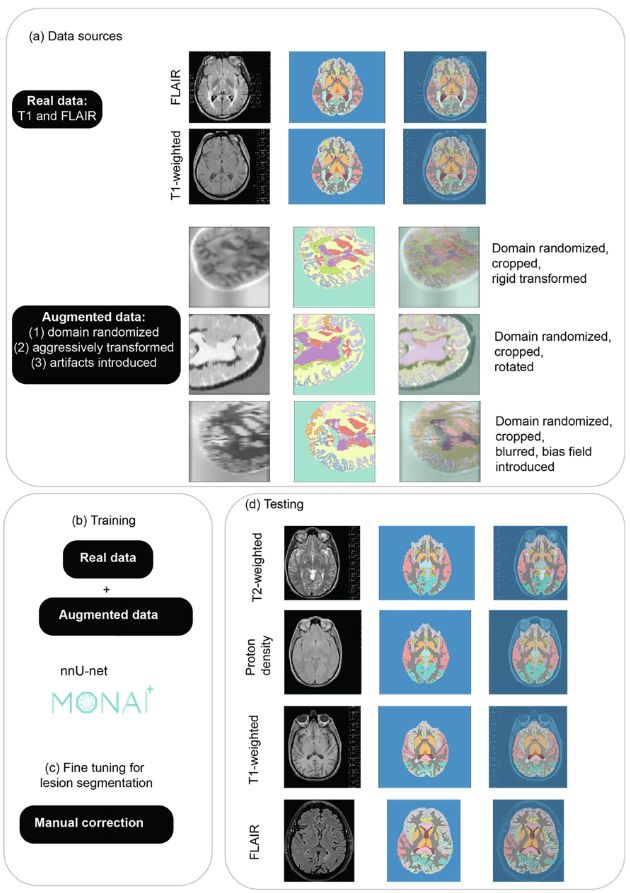

MindGlide 的开发基于「nnU-Net」,这是一种基于 U-Net 架构的 3D 卷积神经网络 (CNN) ,它具有自动自配置的能力,从而可以绕过昂贵的超参数调谐过程。通过训练,MindGlide 可以同时分割脑灰质、白质区域以及 MS 病变,从而适应真实的 MRI 变化,解决传统图像处理软件中的伪影问题。整体架构及策略如下图所示。

MindGlide 训练及外部验证策略的相关步骤

针对模型训练的图像预处理,研究人员使用了一个最小的预处理管道,首先将图像分辨率标准化为 1 mm 各向同性体素,然后根据 nnU-Net 设计。然后研究人员使用滑动窗口技术提取 128 x 128 x 64 体素补丁,以优化训练期间的内存和计算效率。

数据增强主要是通过随机修改人为地扩大训练数据的多样性,增强模型的可泛化性,减轻过拟合。研究人员采用了两种技术用于扩大其适应性,一是扭曲真实扫描的几何形状和图像强度,二是生成合成扫描。如图中 a 所示,采用域随机化,产生强度变化,为不同的 MRI 对比准备模型。

合成数据的生成使用了 SynthSeg 2.0 版本,另外研究人员使用 MONAI 1.2.0 版本在训练期间进行增强,然后直接从训练数据集的标签生成不同对比度的合成扫描。如图中 a 演示了生成的合成数据示例,并在图 b 中展示了通过真实数据和增强数据训练 MindGlide。